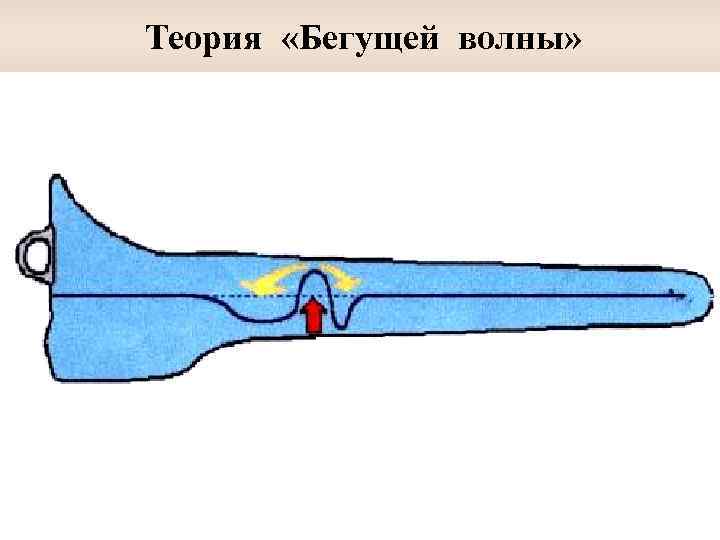

Теория «бегущей волны» Бекеши ü В улитке, помимо обычных волн сжатия, существуют медленные гидродинамические волны ü Они группироваться и усиливаться, образуя частотнозависимые максимумы амплитуды в зависимости от жесткости и упругости базилярной мембраны ü Пространственное распределение частот в базиллярной мембране обусловлено уменьшением ее жесткости и увеличением массы от основного к верхушечному завитку

Теория «Бегущей волны»